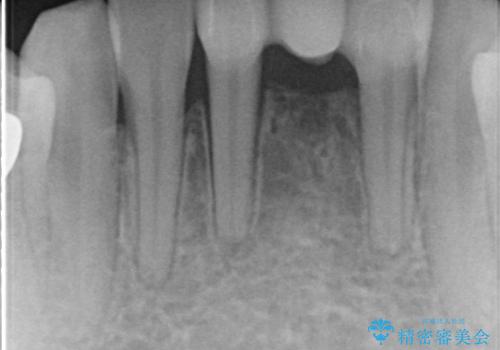

- 晩期残存した下顎乳中切歯の変色を主訴に来院されました。

後続永久歯は先天性欠如しており、下顎前歯のブリッジにて補綴治療を行なっております。